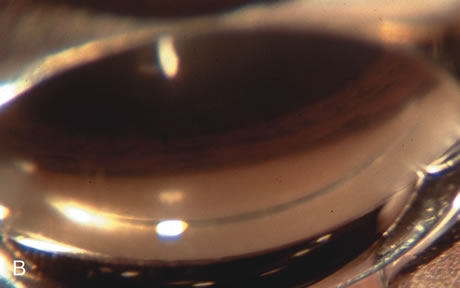

Fig. 4. Viscocanalostomy with deep sclerectomy and phacoemulsification. Nonpenetrating filtration procedures (NPFS) may be combined with phacoemulsification. Patients with mild disc damage and a history of limited topical drug therapy are the best candidates. Patients who require an IOP in the low teens are not good candidates for NPFS. By definition, NPFS is designed to lower IOP without penetrating into the anterior chamber, thereby avoiding the complications associated with trabeculectomy. Viscocanalostomy is intended to allow aqueous to percolate through a trabeculodescemetic membrane into a subscleral cavern created by the deep sclerectomy. The aqueous diffuses from the cavern into the dilated ostia of Schlemm's canal and into the episcleral venous plexus. A. Fashion a uniform 300-micron superficial scleral flap 1 mm into clear cornea. B. Construct a second 600-micron deep flap that facilitates the unroofing of Schlemm's canal, seen as the darker area. C. Use viscoelastic to dilate the ostia of Schlemm's canal. The major problem with viscocanalostomy is the eventual closure of the ostium decreasing flow to the episcleral plexus. D. Dissect the deep flap anteriorly into clear cornea creating the trabeculodescemetic membrane. This membrane is clearly seen between the scleral spur and the bend of the deep flap. The integrity of this membrane ensures the nonpenetrating portion of the surgery. Another problem with NPFS is the eventual fibrosis of this initially transparent membrane requiring goniopuncture. E. Deep sclerectomy gets its name from removal of the deep flap. Removal of this flap creates the potential subscleral space for accumulation of aqueous before it enters Schlemm's canal and exits the episcleral venous plexus. After removal of the deep flap, the superficial flap is sutured into place and conjunctiva closed. Approximately half of these procedures develop a shallow bleb.

Nonpenetrating procedures as they exist today generally decrease postoperative complications but do not reduce IOP as successfully as trabeculectomy.140 The success rate also appears to be highly dependent on race, length of topical antiglaucoma therapy, and prior ocular surgery.141,142 Deep sclerectomy combined with phacoemulsification results in an IOP reduction similar to phacotrabeculectomy at one year with comparable visual outcome.143 Phacoviscocanalostomy lowers IOP by approximately 33%144 through either a one- or two-site approach145 (Fig. 4). Nonpenetrating procedures are in evolution, and their place in long-term glaucoma care is still unclear.